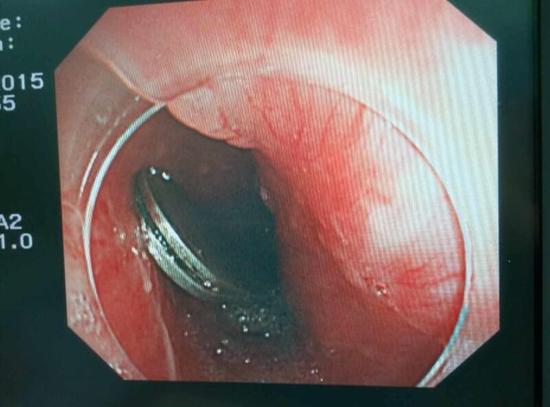

手術(shù)中,范醫(yī)生通過胃鏡準(zhǔn)確發(fā)現(xiàn)了胃里的鑷子。但讓他驚訝的是,在華先生胃底竟然還躺著三個被腐蝕了的打火機,打火機的金屬部件都已經(jīng)不見了。

隨后,范醫(yī)生先用圈套器套取出了長10厘米的鑷子,再一個一個地取出了打火機。整個取出過程小心謹(jǐn)慎而又一氣呵成,只用了不到10分鐘。